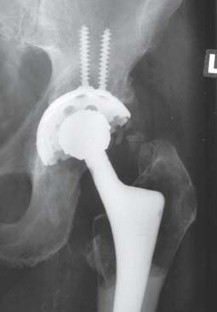

Abb. 3